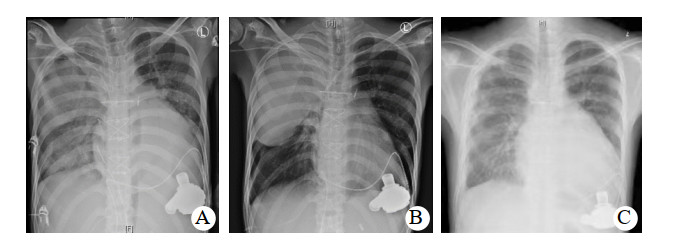

入ICU后查体:血压82/67 mmHg,心率120次/min, 体温36.5℃,呼吸12次/min。双侧瞳孔等大等圆,对光反射迟钝;口唇无发绀,双侧呼吸音粗糙,未闻及干湿啰音。监护提示:窦性心律,心律齐。心前区未闻及心脏杂音;腹平软,肝肋下未触及,肠鸣音弱。四肢末梢皮温正常,足背动脉搏动可及。留置纵隔、心包引流管。入科后即给予了呼吸机辅助呼吸,通气模式采用SIMV/PSV,压力支持12 cmH2O(1 cmH2O=0.098 kPa),呼吸频率12次/min,呼气末正压5 cmH2O, FiO2 0.5,给予舒芬太尼联合右美托咪定镇痛镇静治疗,应用头孢呋辛钠预防切口感染治疗,应用肝素和华法林钠抗凝治疗以及营养支持等综合支持治疗,患者循环稳定,胸片肺淤血较术前减轻,痰不多,于术后第4天顺利脱机拔管,拔管后自主呼吸稳定,少量白稀痰,胸片未见明显变化。术后第7天患者出现体温升高,最高体温38.5℃,痰量增多,为白粘痰,痰中带血,双肺听诊散在痰鸣音,脉搏氧饱和度下降至90%,血气分析提示PaCO2 42 mmHg,PaO2 59 mmHg,实验室检查,PCT 77.87 ng/mL,CRP 198.5 mg/L,患者血压下降,伴有少尿,胸片提示肺感染,经多学科会诊后除外其他部位感染,考虑患者术后合并重症肺炎、呼吸衰竭、感染性休克、急性肾损伤,遂给予再次气管插管机械通气治疗。同时为充分引流痰液,给予了俯卧位通气联合支气管镜肺泡灌洗治疗(俯卧位时间为每次12 h,支气管镜肺泡灌洗每日1次,灌洗剂量为生理盐水100 mL/次),并经验性应用美罗培南联合万古霉素抗感染治疗,给予了液体复苏及CRRT治疗、综合支持治疗。为维持血泵正常运转,继续华林钠口服抗凝治疗,维持INR 2.0~2.5。术后第8天痰培养和血培养均报告为耐碳青霉烯肺炎克雷伯菌,抗生素更改为头孢他啶- 阿维巴坦抗感染治疗。并于术后第15天给患者进行了气管切开治疗。头孢他啶阿维巴坦共应用17 d,期间患者因同时合并了肺部屎肠球菌、热带假丝酵母菌感染,根据药敏实验结果分别给予了替加环素、卡泊芬净等抗感染治疗。因此患者术前反复心衰,营养状况差;术后长期应用抗生素,加上体外循环的打击,机体免疫力差;术后第27天出现菌群失调,严重腹泻,粪便球杆比9 ∶ 1,化验为艰难梭菌感染,给予静脉万古霉素口服(125 mg,q6h)治疗,同时停用所有抗生素。因患者感染未完全控制,继续给予了俯卧位通气联合支气管镜肺泡灌洗治疗,综合营养支持治疗,间断呼吸功能锻炼,患者感染得到有效控制,PCT由77.87 ng/mL下降到0.11 ng/mL,胸片(图 1)及CT(图 2)显示右肺实变影逐渐吸收,术后77 d成功脱离呼吸机辅助,于术后89 d转回普通病房并顺利出院。后期随访患者生活正常。

| 图 1 患者胸片变化 |